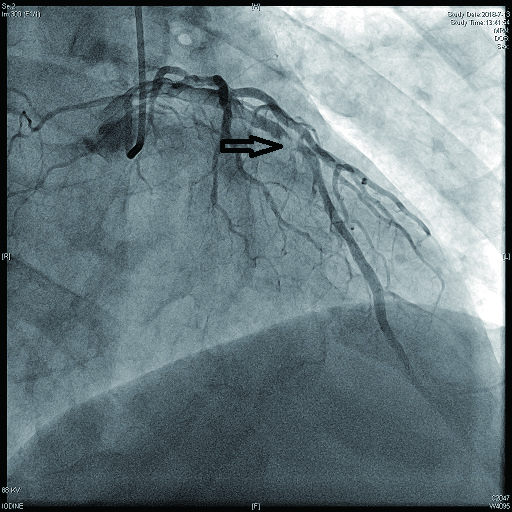

病例2 3(图 6~8 LAD近段 次全闭塞 2级 LAD近段植入支架1枚

图 6 病例2冠脉造影示LAD中段病变

图 7 病例2冠脉造影示LCX病变

图 8 病例2冠脉造影示RCA病变